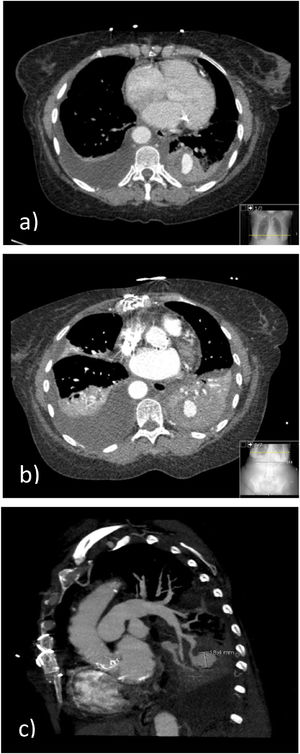

We describe the case of a 67-year-old non-smoker female patient, with a personal history of systemic sclerosis, PH, systemic arterial hypertension, aortic stenosis submitted to biological valve prosthesis placement, epilepsy, and osteoporosis, usually medicated with enalapril, amlodipine, bosentan, pentoxifylline, acetylsalicylic acid, sodium valproate and inhaled fluticasone and salmeterol. The patient was admitted to the ICU due to the development of massive hemoptysis during right cardiac catheterization to measure pulmonary capillary wedge pressure, experiencing cardio-respiratory arrest in asystole treated with advanced life support maneuvers, orotracheal intubation with a large bore single lumen endotracheal tube (ETT), bilateral lung invasive mechanical ventilation and blood transfusion. Bronchoscopy at admission, 48h after the critical episode and on the day of extubation revealed no active bleeding. Chest computed tomography (CT) angiography showed a nodular lesion with contrast enhancement at the level of the posterior segment of the left inferior lobe, suggestive of a pseudoaneurysm with a mural thrombus (Fig. 1A). Given the spontaneous bleeding control after the first episode, and the lack of prompt access to embolic therapy, requiring inter-hospital transportation, priority was given to clinical stabilization and supportive care, with improvement. After extubation, arterial embolization was proposed to prevent recurrence, which the patient refused. A conservative attitude was adopted, according to the patient's wishes, with favorable outcome. Chest CT-angiography on the 7th day (Fig. 1B and 1C) and chest CT, without contrast administration at patient's request, two weeks later, showed PA pseudoaneurysm stability. Six-year follow-up revealed clinical stability with no bleeding recurrence.

(A) Chest CT-angiography at ICU admission. consolidation at the left inferior lobe (LIL) with areas of spontaneous hyperdensity and "ground glass" opacities; Nodular lesion with contrast enhancement, at the posterior segment of the LIL, in continuity with a pulmonary artery tree branch, suggestive of a pseudoaneurysm with a mural thrombus. (B) and (C) Chest CT-angiography (7th day of hospitalization). Pseudoaneurysm arising from the posterior basal branch of the left inferior lobar pulmonary artery; bilateral pleural effusion with passive atelectasis; and consolidation due to hemorrhagic alveolar filling at the LIL.